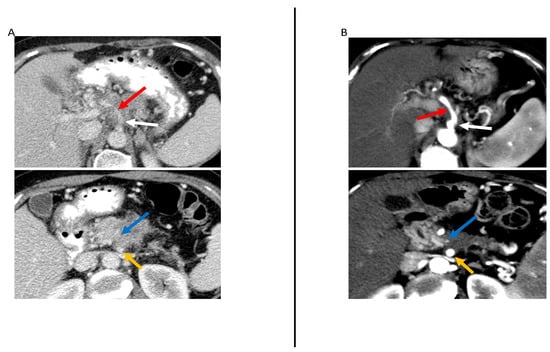

- Amer, A.M.; Zaid, M.; Chaudhury, B.; Elganainy, D.; Lee, Y.; Wilke, C.T.; Cloyd, J.; Wang, H.; Maitra, A.; Wolff, R.A.; et al. Imaging-based biomarkers: Changes in the tumor interface of pancreatic ductal adenocarcinoma on computed tomography scans indicate response to cytotoxic therapy. Cancer 2018, 124, 1701–1709. [Google Scholar] [CrossRef] [PubMed]

| Amer et al. [35], 2018 (U.S.) | 326 | -Response according to RECIST 1.1 criteria -Tumor/pancreas interface response developed by the authors | -Chemo -CRT | 3 radiologists | -Type I vs. Type II response at the interface was significantly associated with fewer viable cells after neoadjuvant therapy and was more likely to achieve major pathologic response (p = 0.01); Type I response also showed improved DFS and OS. |